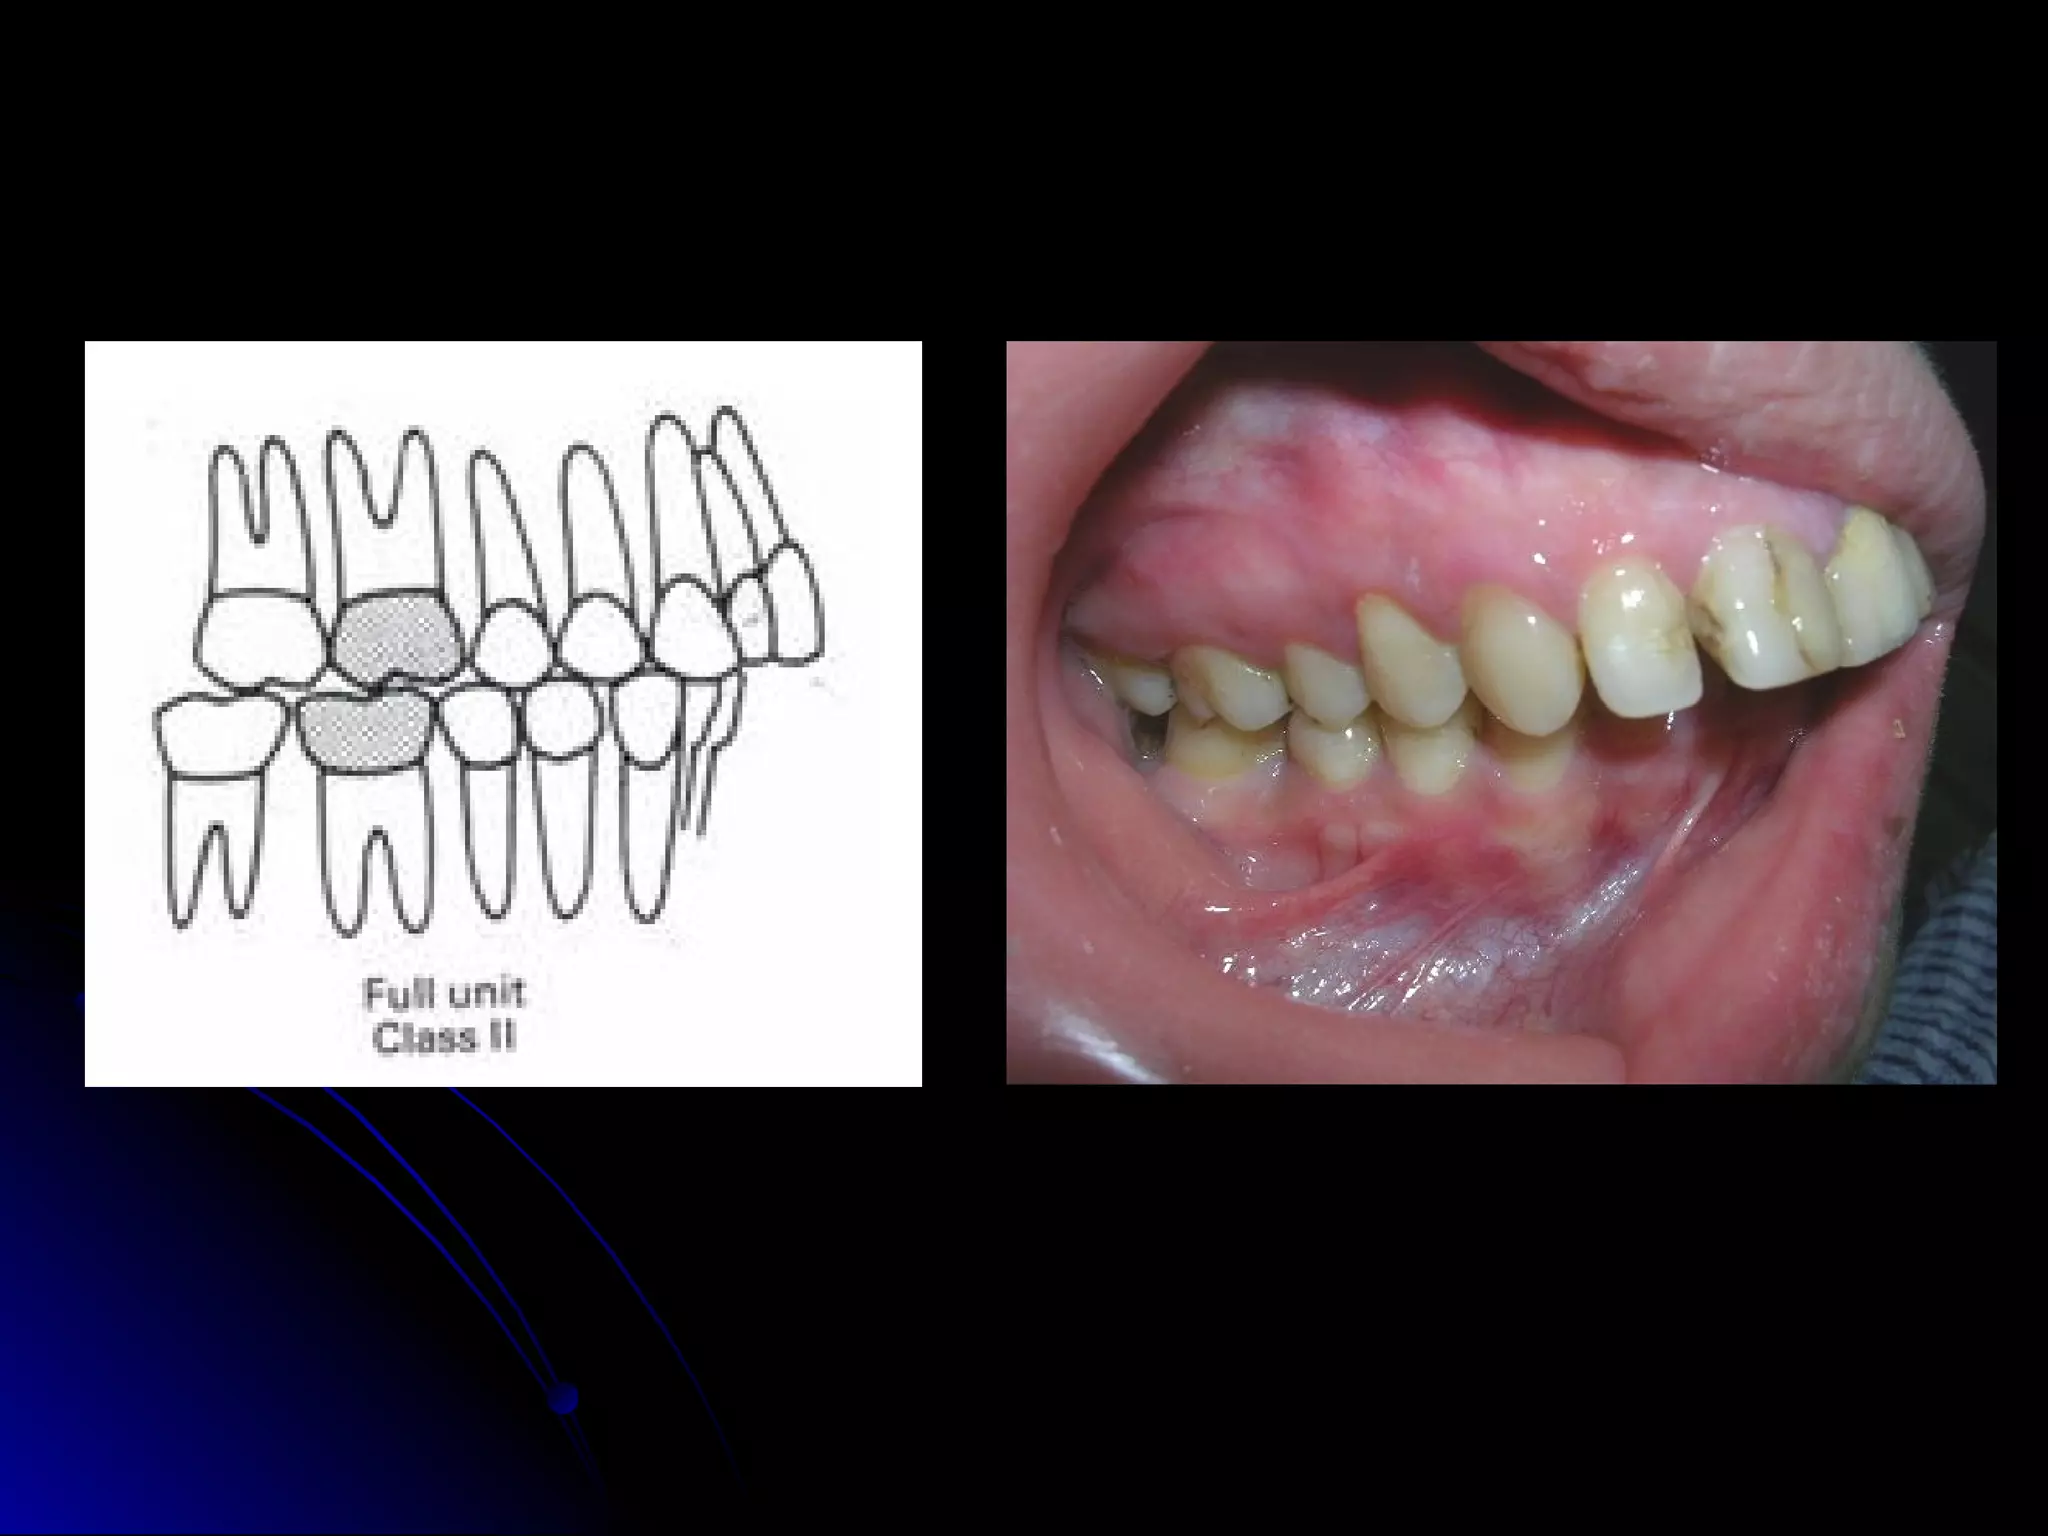

CLASS II MALOCCLUSION

Mesiobuccal cusp of upper first permanent molar

occludes mesial to the buccal develipmental groove of the

lower first permanent molar.

Line of occlusion not specified.

There may be normal or abnormal line of occlusion.

Class II malocclusion is subdivided into two types.

Class II division 1 malocclusion

Molar relation is class II

The upper insisors are proclined.

CLASS II MALOCCLUSION Mesiobuccalcusp of upper first permanent molar occludes mesial to the buccal develipmental groove of the lower first permanent molar. Line of occlusion not specified. There may be normal or abnormal line of occlusion. Class II malocclusion is subdivided into two types.

Class II division1 malocclusion Molar relation is class II The upper insisors are proclined.